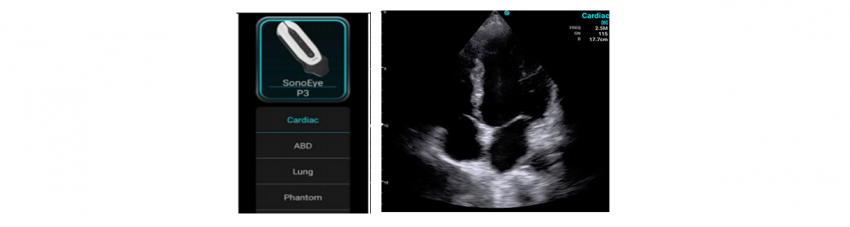

Chison Sonoeye P3 – phased array transducer with a frequency of 1.5 - 4.0 MHz and programs for the abdomen, cardiac, lung examinations.

Philips Lumify S4-1 - phased array transducer with a frequency of 1.0 - 4.0 MHz and a scanning depth up to 30 cm. It has programs for FAST, cardiac, lung, abdominal, obstetrics and gynecology examinations.